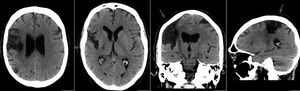

Wallerian degeneration

Physiology

Radiology

Nervous System